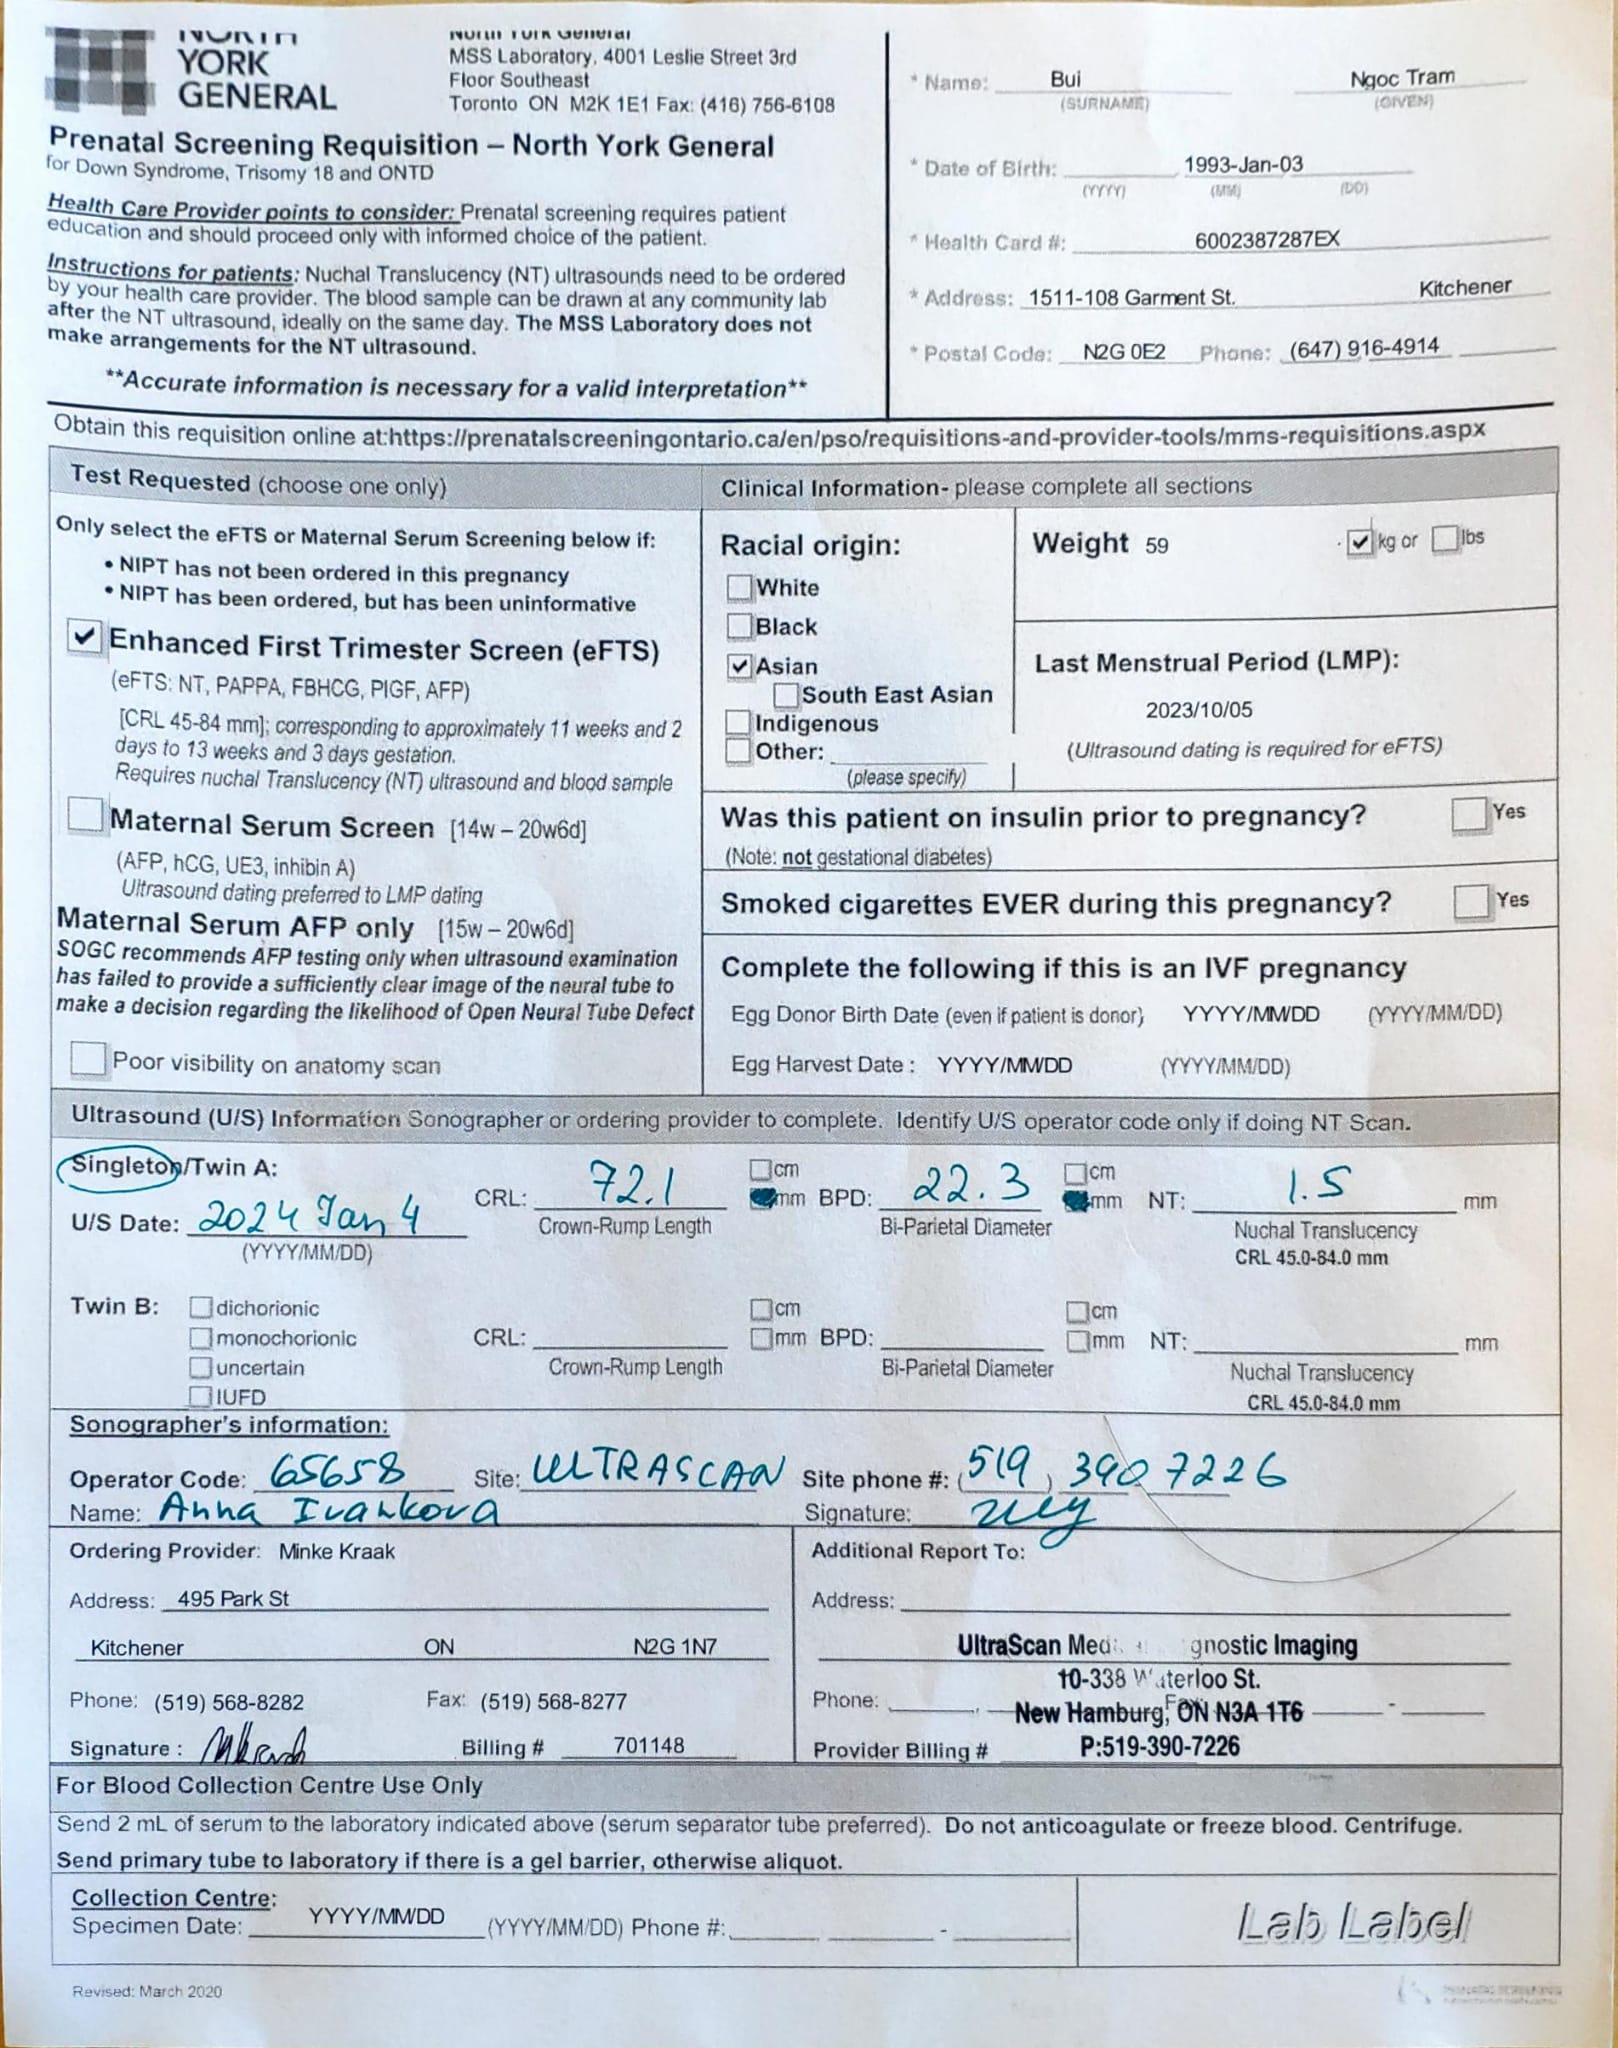

Ultrasound 4 Jan 2024

Sáng sớm 7.30 đã lái xe sang tận New Hamburg để siêu âm con.

Tin vui là con mình khoẻ, con đã có hình hài rồi đây này, nhìn là thương liền.